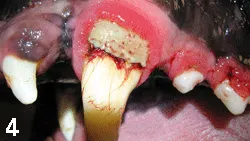

Complications

Complications generally arise only when laser surgery and electrosurgery are used for gingivectomy or gingivoplasty. Proper settings, operator experience, and precise technique are paramount if these methods are chosen. Thermal necrosis of gingival tissue, bone, and teeth can result when these methods are used improperly (Figure 4).

Figure 4

Thermal necrosis in a patient treated for gingival hyperplasia using radiosurgery. Generalized bone, soft tissue, and pulp necrosis resulted in multiple extractions.